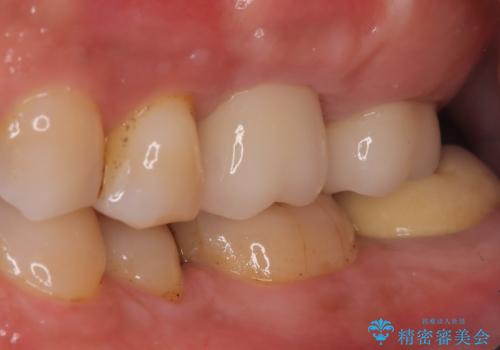

【歯牙破折】インプラントによる咬合回復

- 痛みを主訴に来院されました。

歯牙の破折を認めたため抜歯をし、インプラントにて咬合回復をしました。

抜歯後、骨増生を行ったのちインプラントを埋入しています。